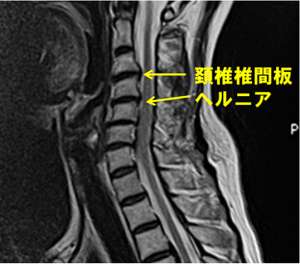

頚椎ヘルニアとは、

・椎間板(クッション)が飛び出す

・神経を圧迫する

ことで症状が出る状態です。

① 画像検査(MRI・レントゲン)

ヘルニアの位置・大きさを確認